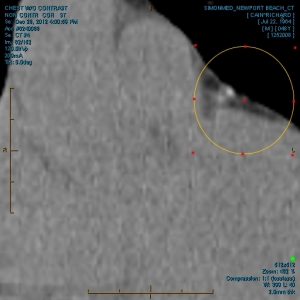

“Please take a look at both X-rays. Superimpose the foreign objects AKA EKG clamps and you will find that they are the same devices. when have you ever seen an EKG clamp place sideways in the abdomen? Both x-rays have been confirmed by Radiologist Louis Teresi as having foreign body reactions in the abdomen, right and left flanks.

“The obvious implant in the 2012 x-ray stands out from the others, because it at the time had not embedded into my flesh (heart).”